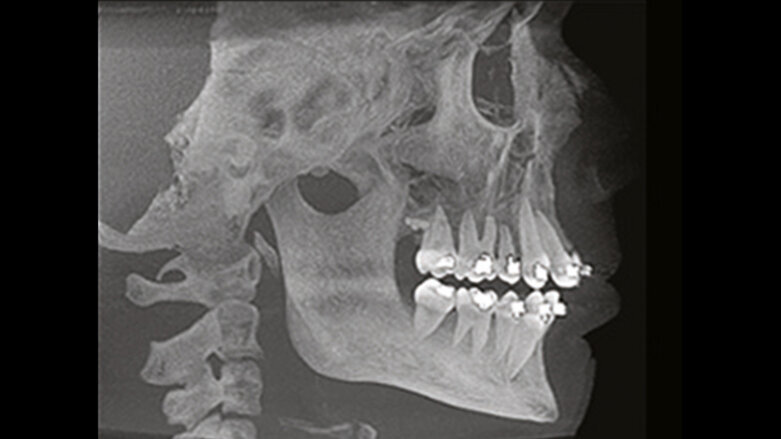

Kefalometrické pohledy konstruované z 3D skenování (obrázek publikován se svolením i-CAT)